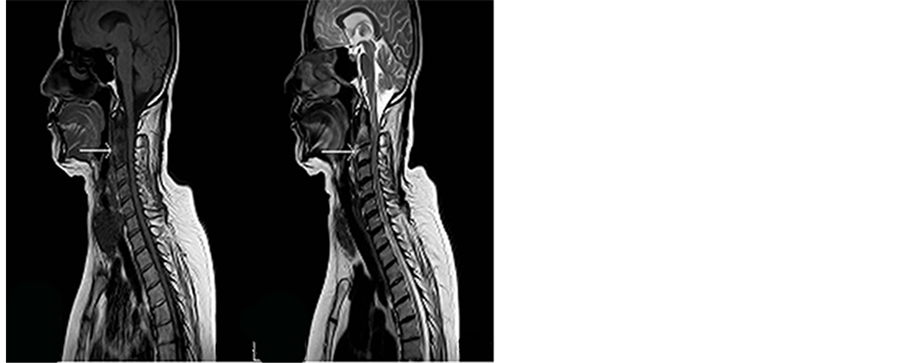

Her swallowing difficulties improved. However, one month after the initial accident, she developed neck pain radiating to both shoulders associated with low grade fever, she also complained of chest pain. A cervical spine MRI revealed a 2.5 × 1 × 0.5 cm anterior epidural and retropharyngeal abscess at the level of C2-C3 associated to compression of the spinal cord. She was started on Vancomycin (1 g q12h) and Meropenem (1 g q8h), but was shifted to Ciprofloxacin (750 mg q12h) and Tigecycline (100 mg then 50 mg every 12 hours) after she developed a diffuse rash. No surgical intervention was done at this stage. A repeat MRI two weeks later, revealed an increase in the epidural abscess size with progression of the spinal cord compression with evidence of C2-C3 frank osteomyelitis (Figure 1(a), Figure 1(b)).

Figure 1. (a) Preop T1 WI MRI; (b) Pre operation T2 WI MRI.